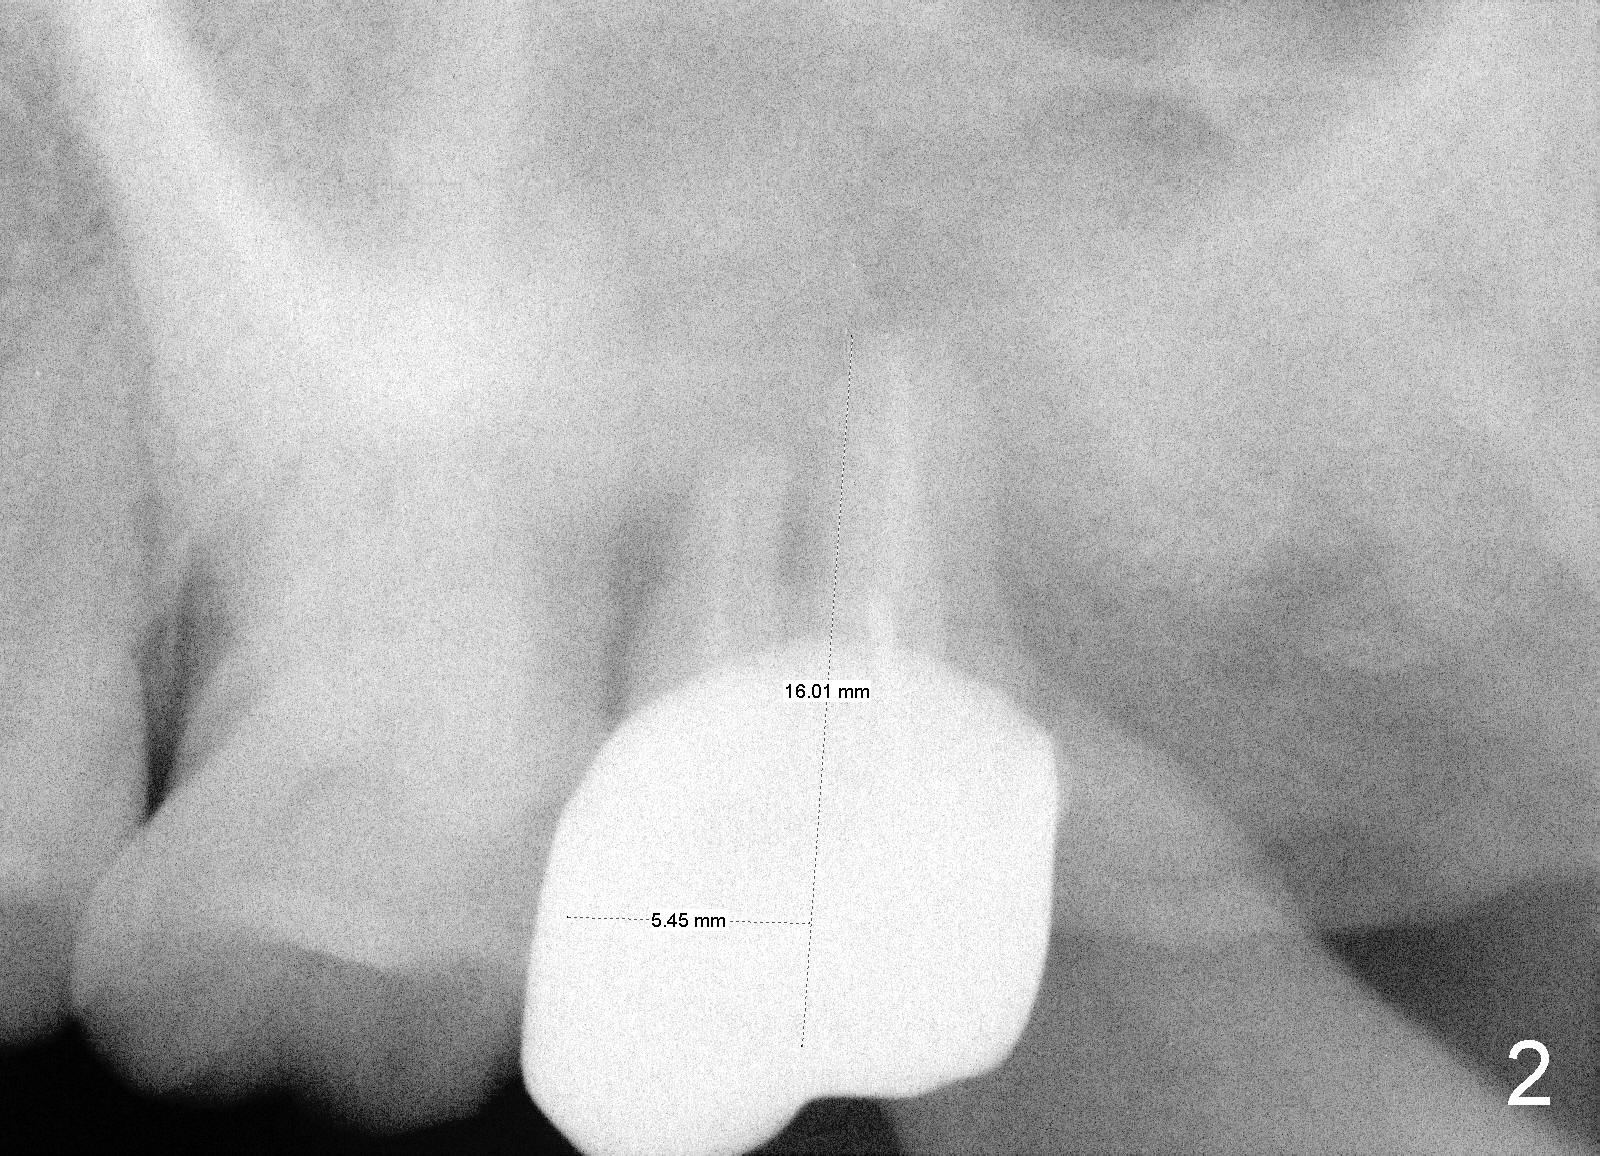

The vertigo does disappear pretty soon.  The patient is pleased with the implant.  PAs are taken 7 months (Fig.5,6 arrowheads: sinus floor) and 1 year 7 months (Fig.7,8) post cementation.  The tooth #14 has furcation infection (Fig.8). Back to Professionals Follow up Xin Wei, DDS, PhD, MS 1st edition 01/29/2013, last revision 08/11/2019